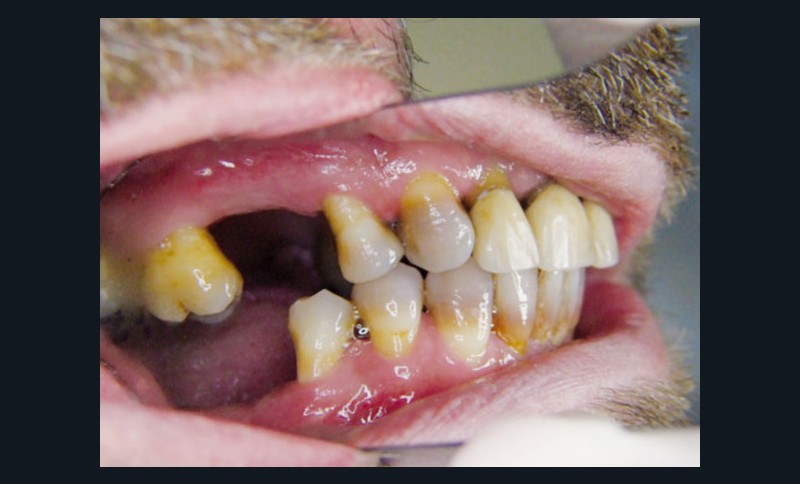

L’examen clinique du patient en consultation d’implantologie débutera donc par un examen visuel du site et se poursuivra par une palpation de la région (fig. 1).

La largeur de la crête sera alors estimée mais seule l’analyse d’un cliché radiographique en 3D de type Cone Beam (CBCT) sera à même de préciser le volume osseux disponible. En cas d’insuffisance, de volume osseux vertical une élévation de sinus pourra être proposée (fig. 2).